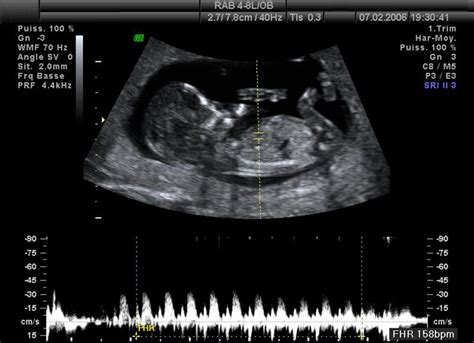

Prvý ultrazvuk - sa nazýva prenatálny skríning a robí sa v 11. až 13. týždni. Tento ultrazvuk je najdôležitejší, pretože dokáže najskôr odhaliť prípadné odchýlky vo vývoji a oboznámiť rodičov o tom, či je dieťa v poriadku. Počas neho sa vykonáva i šijové presvietenie, ktoré je najpresnejším vyšetrením v tomto smere. V podstate ak by bol tento prvý ultrazvuk v poriadku, mamička by sa už nemala obávať.

Ultrazvukové vyšetrenie v prvom trimestri tehotenstva je kľúčovým krokom k zabezpečeniu zdravého vývoja Vášho dieťatka. Vyšetrenie sa vykonáva medzi 12. až 14. týždňom tehotenstva, kedy plod meria medzi 45 - 84 mm od hlavičky k zadočku. V rámci tohto dôležitého vyšetrenia, ktoré vykonáva MUDr. Kristína Bihariová vo Zvolene, sa zameriavame na viaceré dôležité aspekty: Vaginálne vyšetrenie: V úvodnej časti vyšetrenia, ktorá prebieha vaginálnym prístupom, sa zameriavame na dĺžku hrdla maternice. Týmto spôsobom vieme vylúčiť hroziaci predčasný pôrod a posúdiť prietoky v oblasti uterinných ciev. Tieto cievy sú zodpovedné za zásobovanie maternice a placenty krvou. Meraním toku krvi dokážeme určiť mieru rizika pre vznik preeklampsie, čo je ochorenie špecifické pre tehotenstvo. V prípade zvýšeného rizika vieme nasadiť liečbu, ktorá toto riziko znižuje. Brušné vyšetrenie: V druhej časti vyšetrenia, ktorá prebieha brušnou cestou, sa podrobne vyšetruje bábätko. Kontrolujeme tvar lebky a štruktúry mozgu, tváričku, prítomnosť nosovej kosti (NB - z angl. nasal bone), prejasnenie v oblasti šije (NT - z angl. nuchal translucency) a prítomnosť intrakraniálnej translucencie (IT), ktorá pomáha vylúčiť rázštep chrbtice. Dôkladne sa posudzujú aj končatiny, orgány brušnej dutiny, pupočník, cieva ductus venosus (DV) a v základnej anatómii aj srdiečko plodu. Po zadaní všetkých týchto údajov do špeciálneho programu, akým je Astraia, vypočítame individuálne riziko pre prítomnosť chromozomálneho ochorenia dieťatka, ako je Downov, Edwardsov a Patauov syndróm. Okrem toho vypočítame aj riziko pre vznik preeklampsie a rastového zaostávania plodu z dôvodu nedostatočnej výživy placentou. Toto vypočítané riziko je možné ešte spresniť, ak má budúca mamička k dispozícii aj výsledok tzv. PAPP testu.

Ideálna doba na vyšetrenie je medzi 12. - 14. týždňom a 20. - 28. týždňom tehotenstva. Táto váha je vypočítaná na základe merania priemeru a obvodu hlavičky, obvodu bruška a dĺžky stehnovej kosti. V rámci tohto detailného vyšetrenia, ktoré vykonáva MUDr. Kristína Bihariová vo Zvolene, sa zameriavame na viacero dôležitých aspektov: Vaginálne vyšetrenie: Vyšetrenie začíname vaginálnym prístupom, aby sme posúdili dĺžku hrdla maternice a prietoky v oblasti materničných ciev. Týmto spôsobom dokážeme vyhodnotiť riziko predčasného pôrodu a preeklampsie, čo sú dôležité faktory pre zdravie mamičky aj bábätka. Brušné vyšetrenie: Následne pokračujeme vyšetrením plodu cez bruško tehotnej. Počas tohto vyšetrenia podrobne hodnotíme anatómiu orgánov bábätka: mozgu, tváričky, hrudníka, bruška, panvy, končatín a chrbtice.